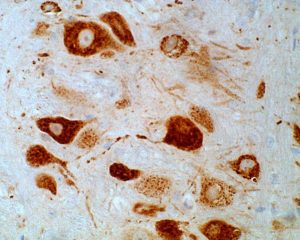

Once infected by virus, nerve cells of the brain will attract large numbers of white blood cells to clear the infection. Among these, a primitive group known as monocytes, newly minted by the bone marrow, causes inflammation that amplifies the immune response. However, this behaviour can also cause lethal damage. In a novel therapeutic strategy, we have used immune modifying nanoparticles to modulate monocyte migration and function, to reduce inflammation, increase healing and enable survival, not just in viral infection of the brain, but in a range of other diseases in which inflammation is excessive.

Once infected by virus, nerve cells of the brain will attract large numbers of white blood cells to clear the infection. Among these, a primitive group known as monocytes, newly minted by the bone marrow, causes inflammation that amplifies the immune response. However, this behaviour can also cause lethal damage. In a novel therapeutic strategy, we have used immune modifying nanoparticles to modulate monocyte migration and function, to reduce inflammation, increase healing and enable survival, not just in viral infection of the brain, but in a range of other diseases in which inflammation is excessive.